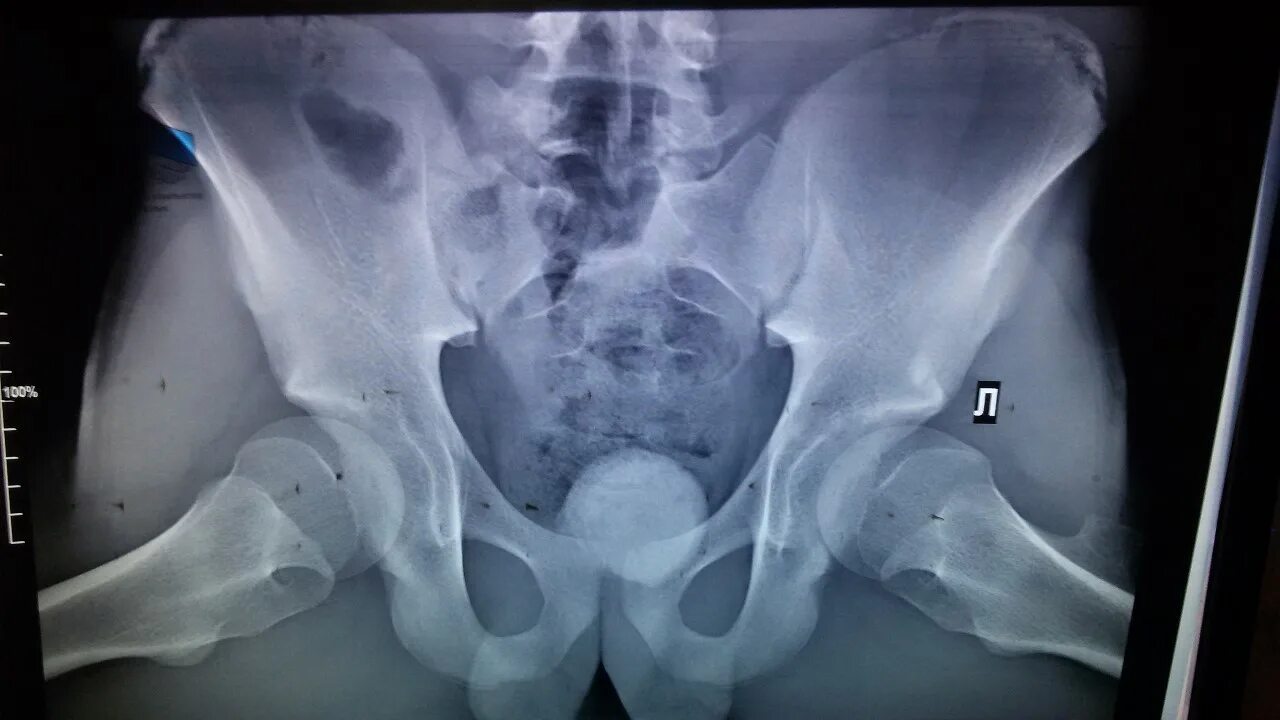

Можно вылечить дисплазию